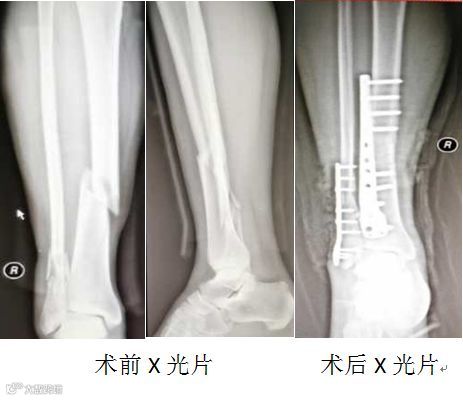

61岁男性患者,因“在家摔倒致右小腿疼痛、活动受限2小时”入院。

诊断:右胫腓骨粉碎性骨折。

行右胫腓骨骨折切开复位钢板螺钉内固定术,术后患者恢复良好。